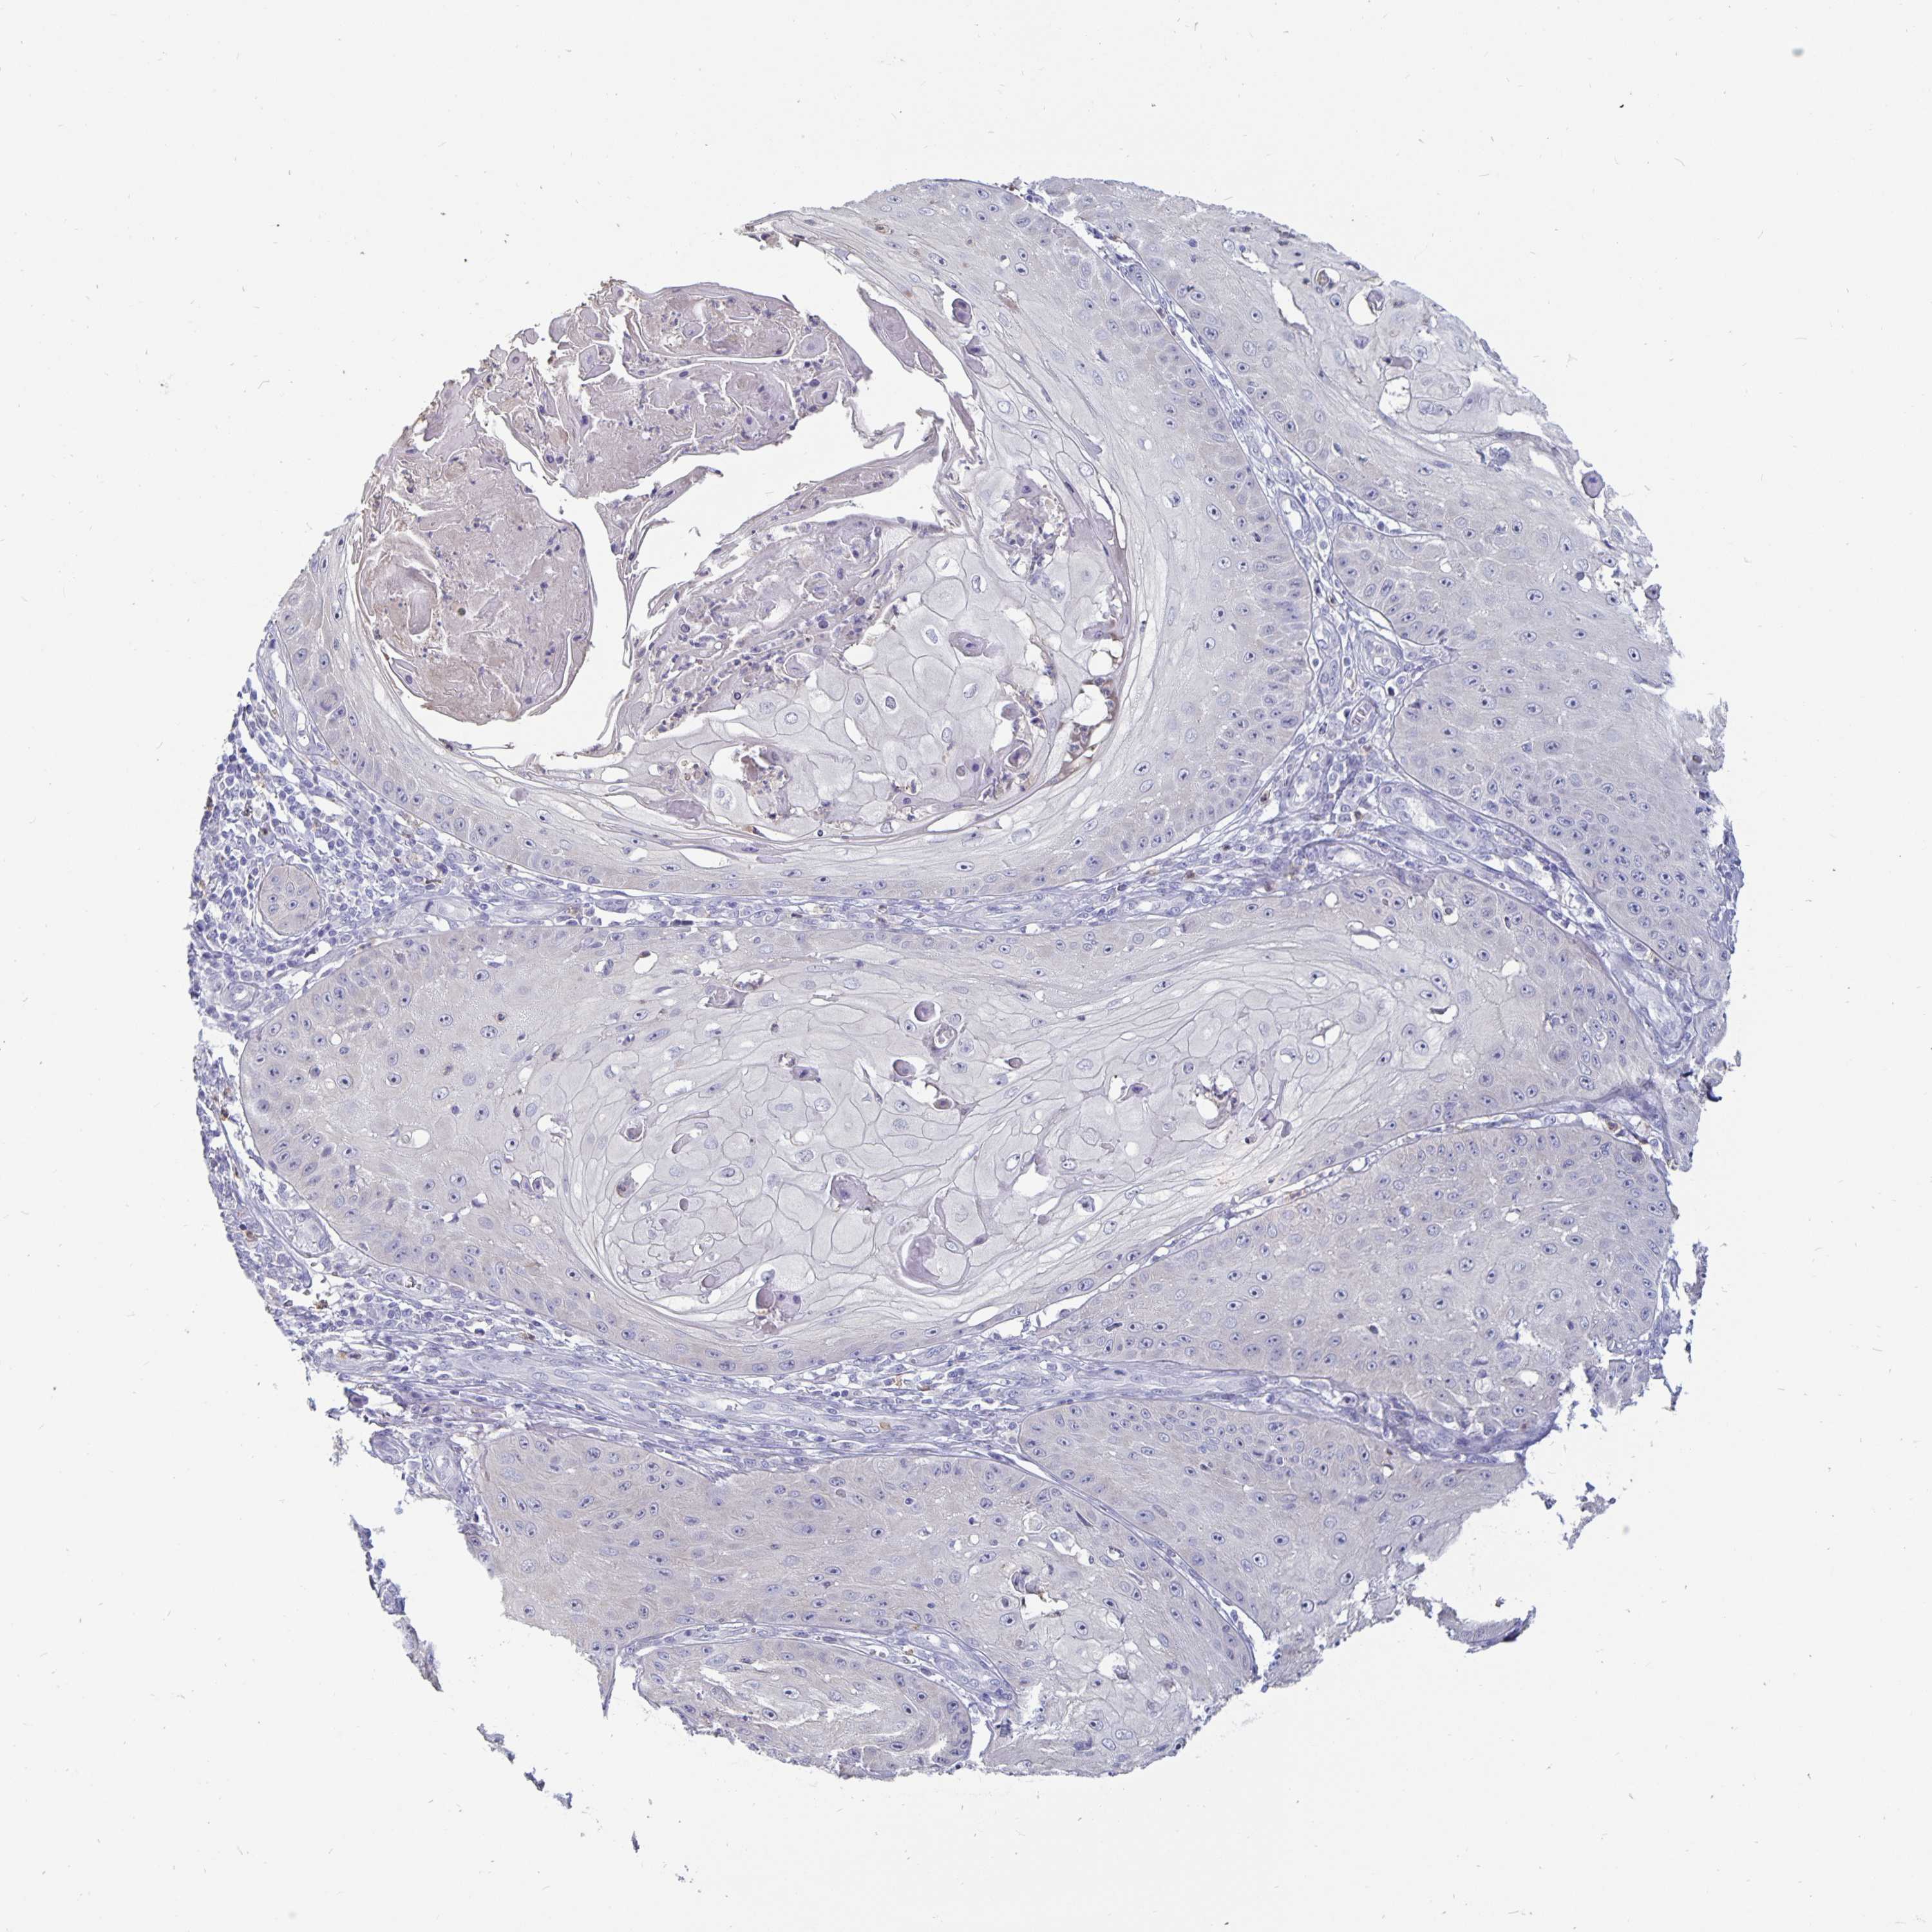

SKIN CANCER - Protein expressioni

A mouse-over function shows sample information and annotation data. Click on an image to view it in a full screen mode. Samples can be filtered based on level of antibody staining by selecting one or several of the following categories: high, medium, low and not detected. The assay and annotation is described here.

Antibody staining in the annotated cell types in the current human tissue is reported as not detected, low, medium, or high, based on conventional immunohistochemistry profiling in selected tissues. This score is based on the combination of the staining intensity and fraction of stained cells.

Each image is clickable and will lead to virtual microscopy that enables deeper exploration of all samples and also displays staining intensity scores, fraction scores and subcellular localization as well as patient and tissue information for each sample.

Antibody HPA039279

Antibody HPA043907

Antibody CAB009257

Basal cell carcinoma

BCC, high aggressive

Squamous cell carcinoma, NOS